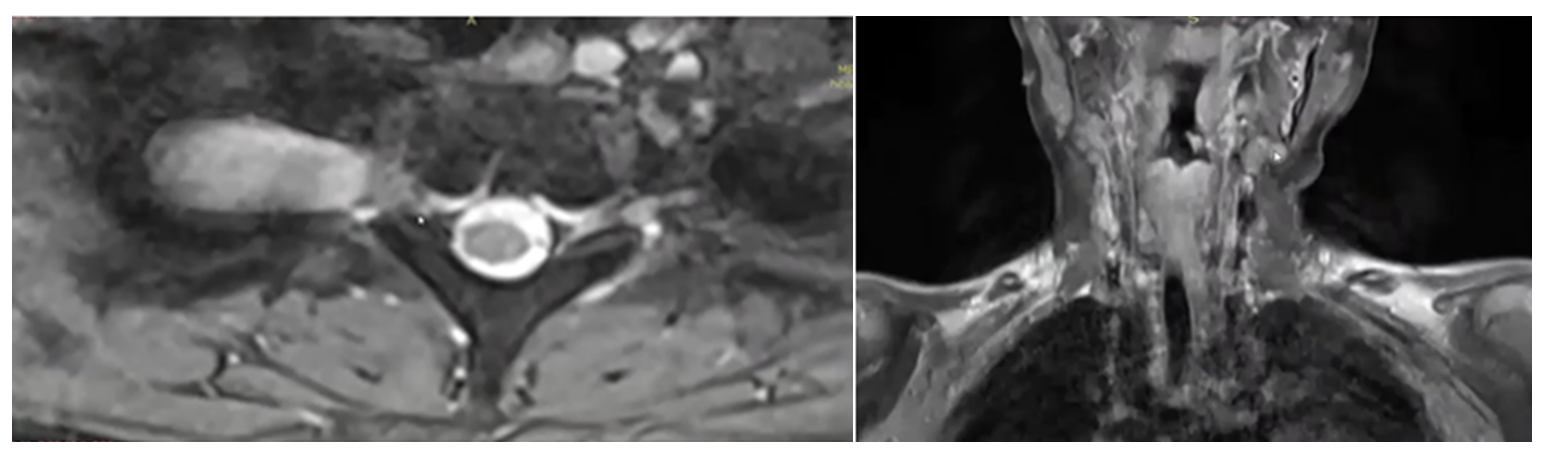

患兒頸胸段、腰段等多處出現結節

由於當時社會對這個罕見病的關注度較低,而且孩子並未表現出身體不適,醫生和家長因此也未過多關注。隨着年齡增長,軒軒身上的咖啡斑和色素沉着越發明顯,潛藏在體內深部的瘤體也明顯增大,並且逐漸出現了新發病灶,包括頸部、脊椎旁,骶管、盆腔等。